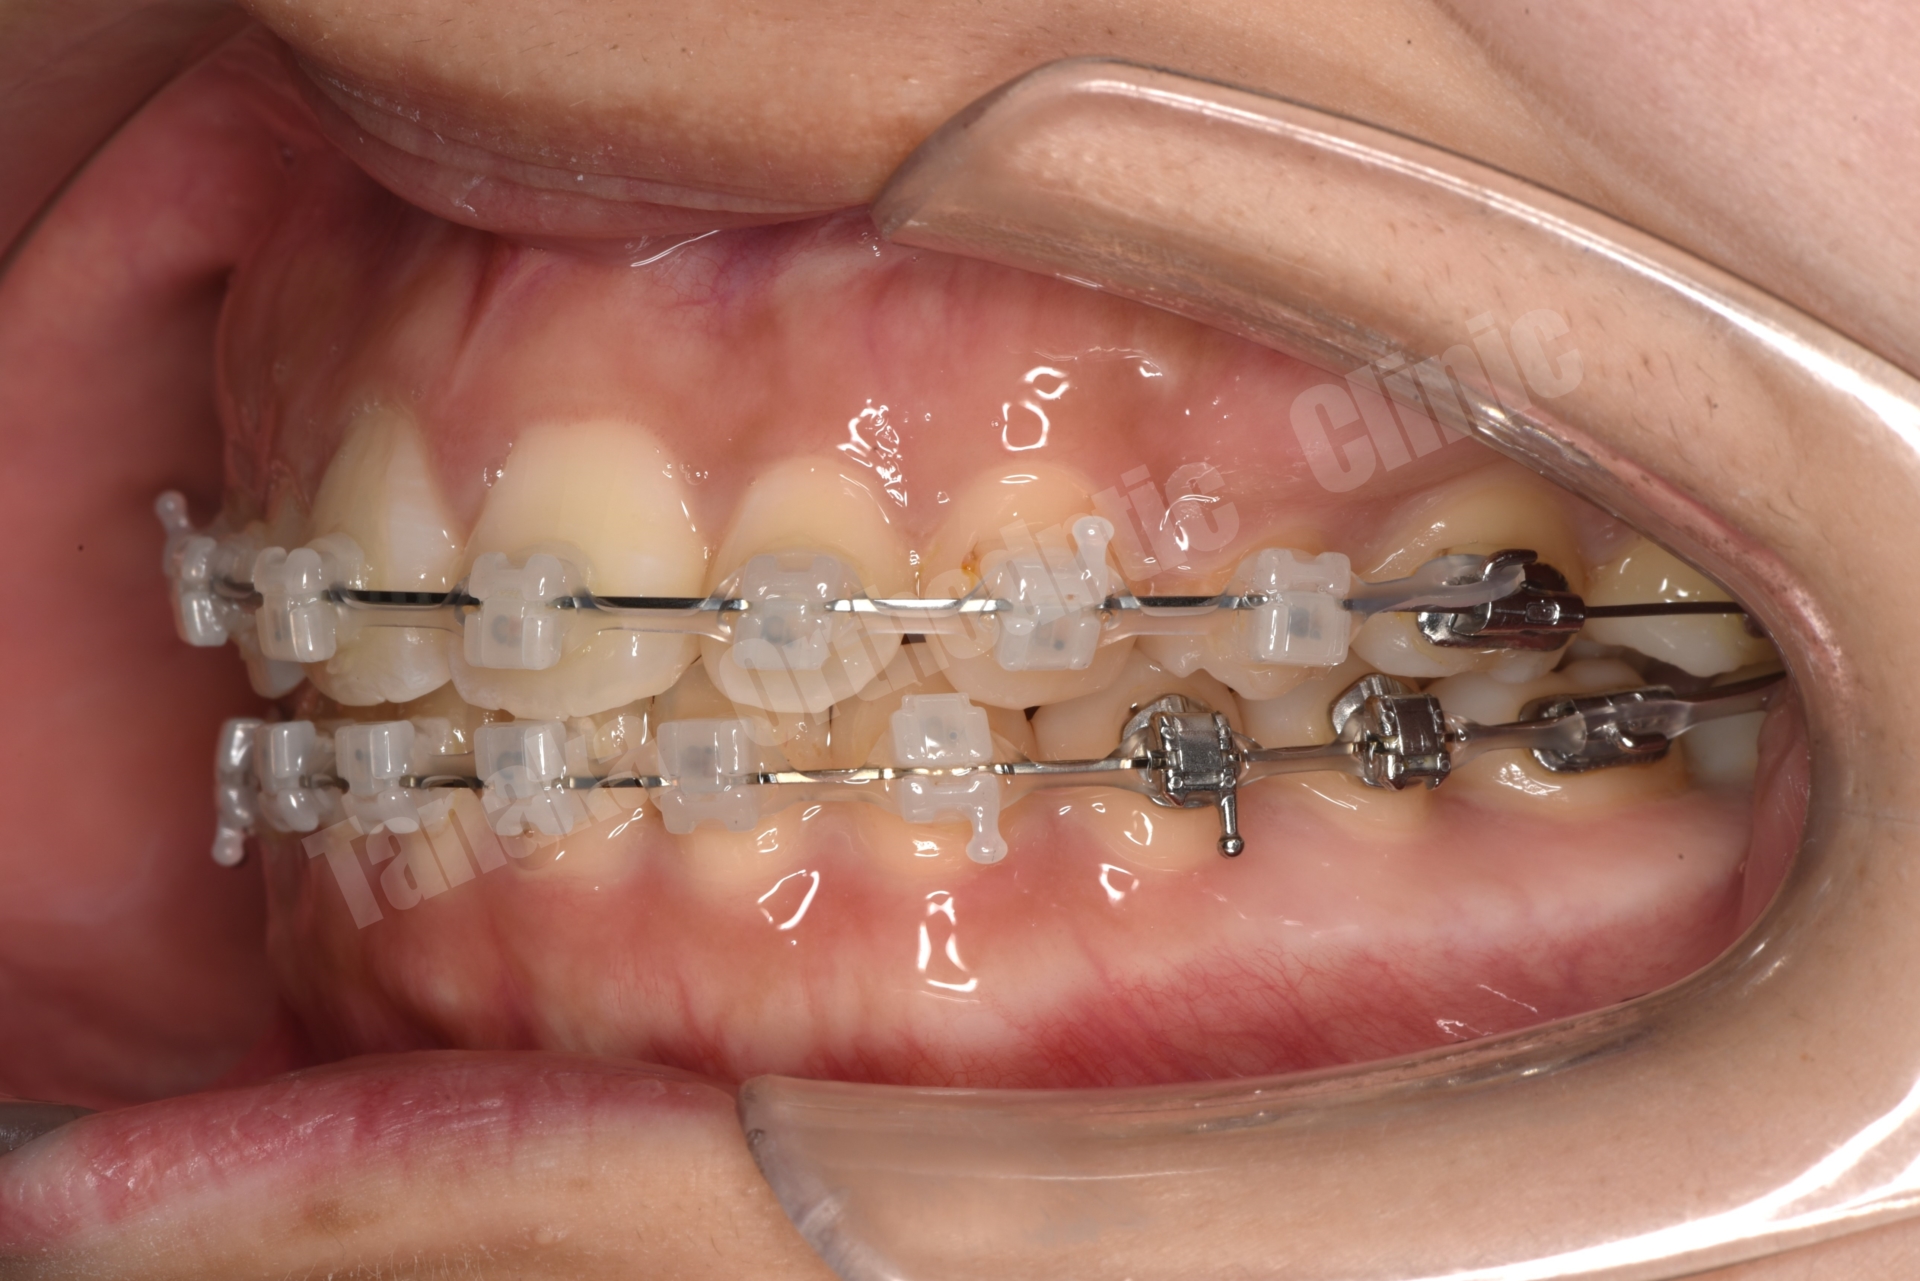

そこで治療では上下歯列に唇側マルチブラケット装置を装着し、歯列全体の排列を行いました。上顎前突を改善するため上顎両側4番を抜歯し、前歯を後退させて口元のバランスを整える計画としました。さらに下顎正中の改善のため右下Eを抜歯し、約11mmある乳臼歯部のスペース閉鎖を行う計画としました。このスペース閉鎖には矯正用アンカースクリューを使用し、右側6番・7番を近心移動させる必要があります。また治療途中で萌出してくる右下7番の位置を適切にコントロールすることも重要なポイントとなります。

今回の症例では、11mmという比較的大きなスペース閉鎖に加え、治療途中で萌出してくる7番のコントロールも必要となるため、通常より難易度の高い治療となりました。そのため治療期間は通常よりやや長くなる可能性を考慮し、2年以内での治療終了を目標として治療を開始しました。

結果として歯の移動は順調に進み、約1年8か月で治療を終了することができました。気になっていた上顎前歯の突出感と側貌は改善し、前歯の咬み合わせも回復しました。また右下乳臼歯部のスペースを閉鎖することで、将来的にインプラントなどの補綴処置が必要になる可能性も回避することができました。